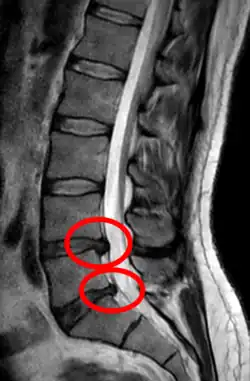

Lumbar disc herniation

Herniated lumbar disc

Lumbar disc herniations occur in the back, most often between the fourth and fifth lumbar vertebral bodies or between the fifth and the sacrum. Here, symptoms can be felt in the lower back, buttocks, thigh, anal/genital region (via the perineal nerve), and may radiate into the foot and/or toe. The sciatic nerve is the most commonly affected nerve, causing symptoms of sciatica. The femoral nerve can also be affected and cause the patient to experience a numb, tingling feeling throughout one or both legs and even feet or a burning feeling in the hips and legs.[22] A herniation in the lumbar region often compresses the nerve root exiting at the level below the disc. Thus, a herniation of the L4–5 disc compresses the L5 nerve root, only if the herniation is posterolateral.

• Magnetic resonance imaging is the gold standard study for confirming a suspected LDH. With a diagnostic accuracy of 97%, it is the most sensitive study to visualize a herniated disc due to its significant ability in soft tissue visualization. MRI also has higher inter-observer reliability than other imaging modalities. It suggests disc herniation when it shows an increased T2-weighted signal at the posterior 10% of the disc. Degenerative disc diseases have shown a correlation with Modic type 1 changes. When evaluating for postoperative lumbar radiculopathies, the recommendation is that the MRI is performed with contrast unless otherwise contraindicated. MRI is more effective than CT in distinguishing inflammatory, malignant, or inflammatory etiologies of LDH. It is indicated relatively early in the course of evaluation (<8 weeks) when the patient presents with relative indications like significant pain, neurological motor deficits, and cauda equina syndrome. Diffusion tensor imaging is a type of MRI sequence used for detecting microstructural changes in the nerve root. It may be beneficial in understanding the changes that occur after herniated lumbar disc compresses a nerve root, and might help in differentiating the patients that need surgical intervention. In patients with a high suspicion of radiculopathy due to lumbar disc herniation, yet the MRI is equivocal or negative, nerve conduction studies are indicated.[46] T2-weighted images allow for clear visualization of protruded disc material in the spinal canal.